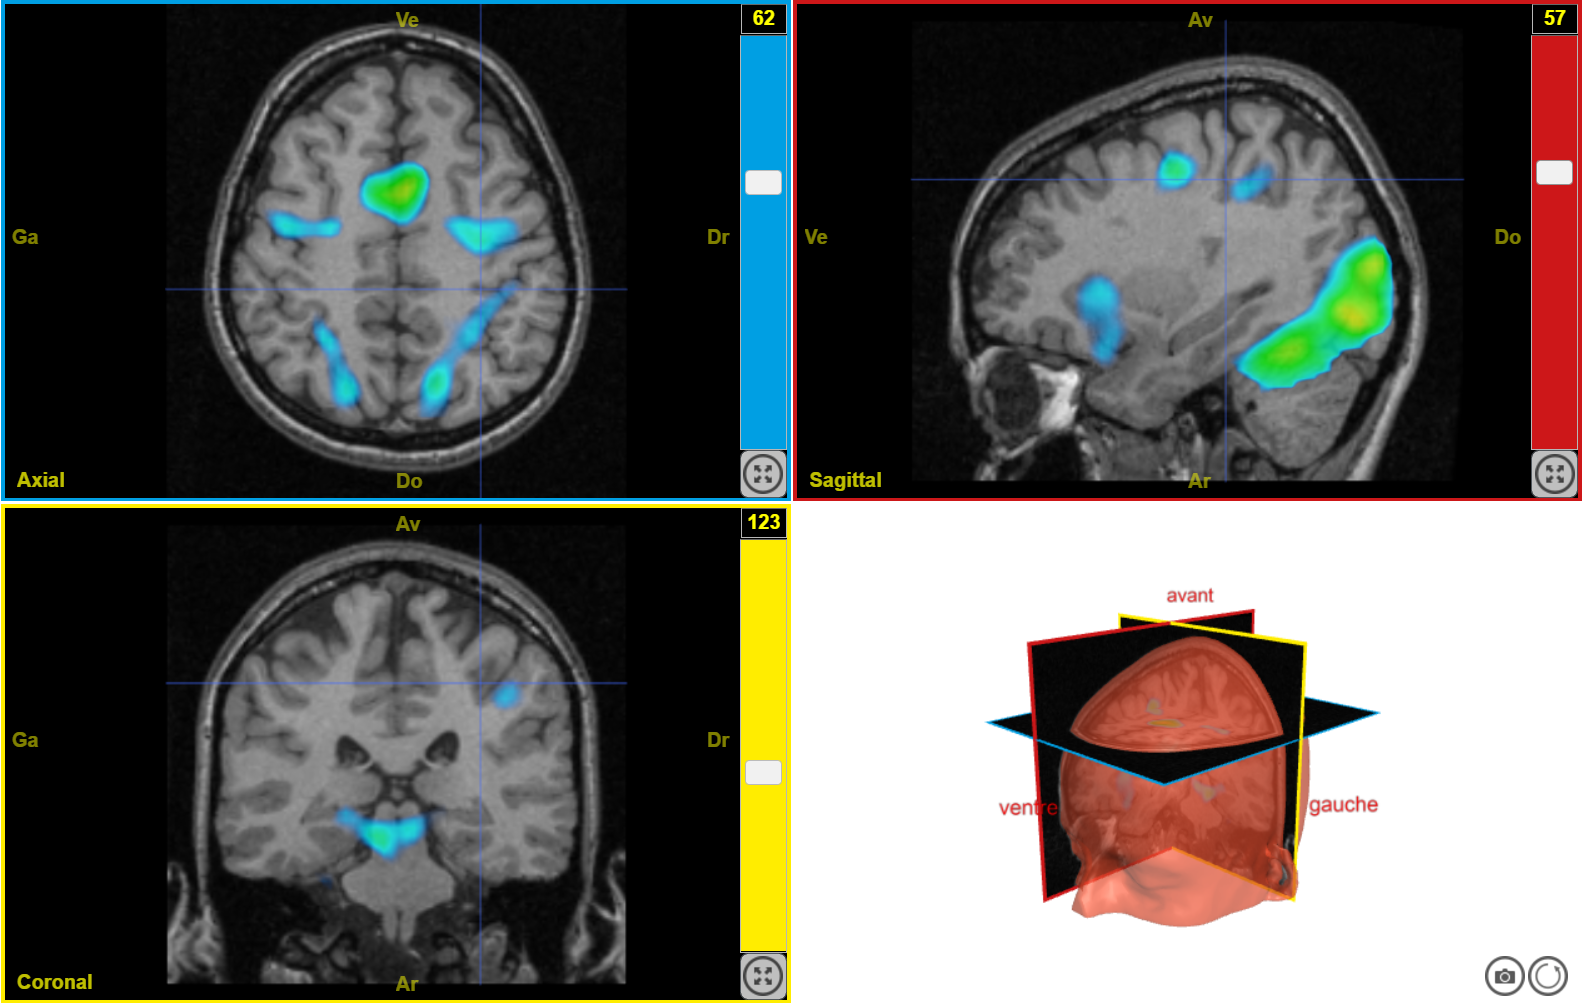

plaisir2

Image dans sa taille originale :

637 ko